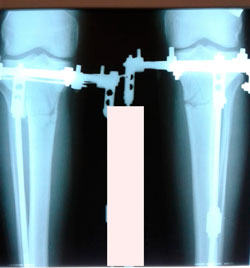

Исходник - 29 лет.

Дата операции - 29.09.2020

Мальчик